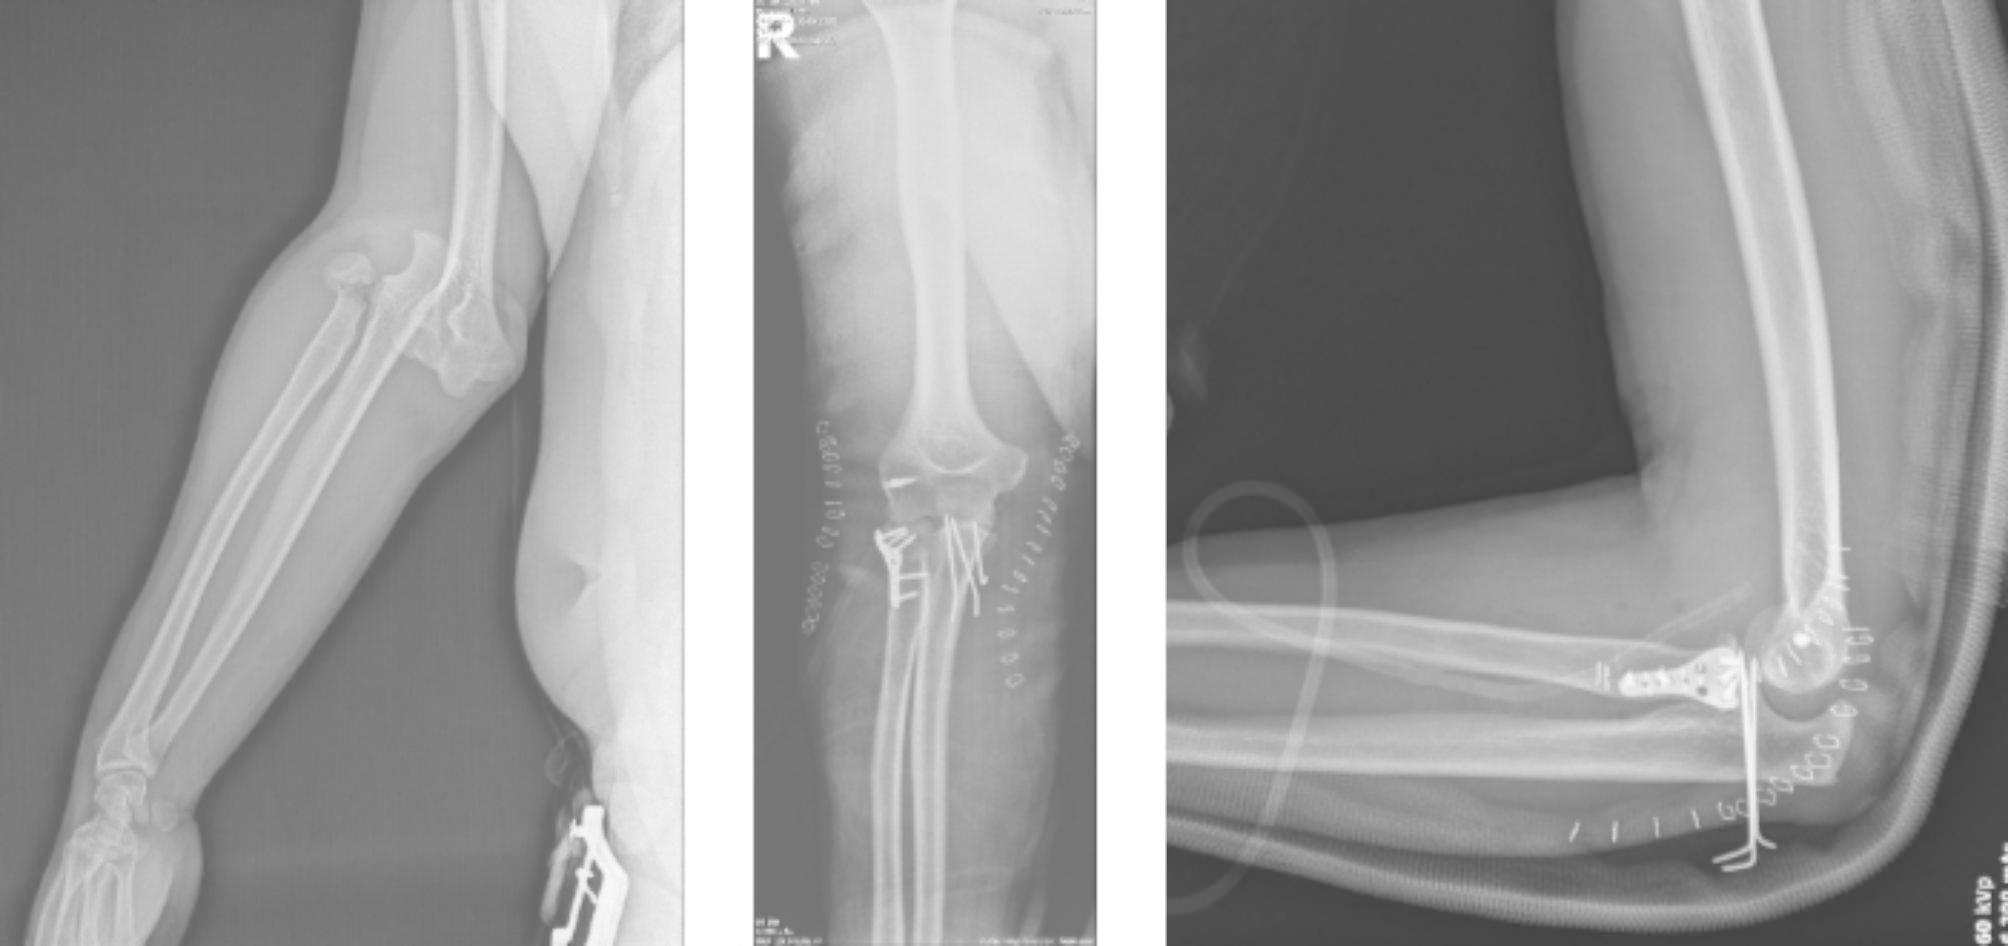

To the best of our knowledge, this study is the first to have evaluated orthopedics-related injuries after e-scooter accidents in Turkey. In particular, people’s avoidance of public transport during the COVID-19 pandemic, the transition to a shared e-scooter system in many big cities, and cheap and easy use have made the use of e-scooters widespread among the public. However, the number of accidents has increased rapidly. As seen in this study, various traumas that affect human life, including death, may occur after using e scooters. From the study results, it was observed that 32 (61.5%) patients were operated on due to fractures and dislocations after the accident (Figs. 2 and 3). In a study by Cruz et al., surgery was performed on 30.1% of the patients and it was shown that the use of e-scooters caused high-energy injuries such as femoral neck fractures, open lower and upper extremity fractures, and fracture-dislocations [10]. In another study, major musculoskeletal injuries were observed at the rate of 36% after e-scooter accidents [11]. Mayhew et al. reported that orthopedic injuries after e-scooter accidents were the most common pathology at the rate of 20.6% [1]. Similar to the current study, previous studies have shown that the most common fractures after an e-scooter accident are upper extremity fractures [8, 10, 12].

Fig. 2

A 23-year-old male patient with elbow fracture dislocation (terrible triad) after falling from e-scooter. (A) Preoperative antero-posterior radiography, (B) Postoperative antero-posterior radiography, (C) Postoperative lateral radiography